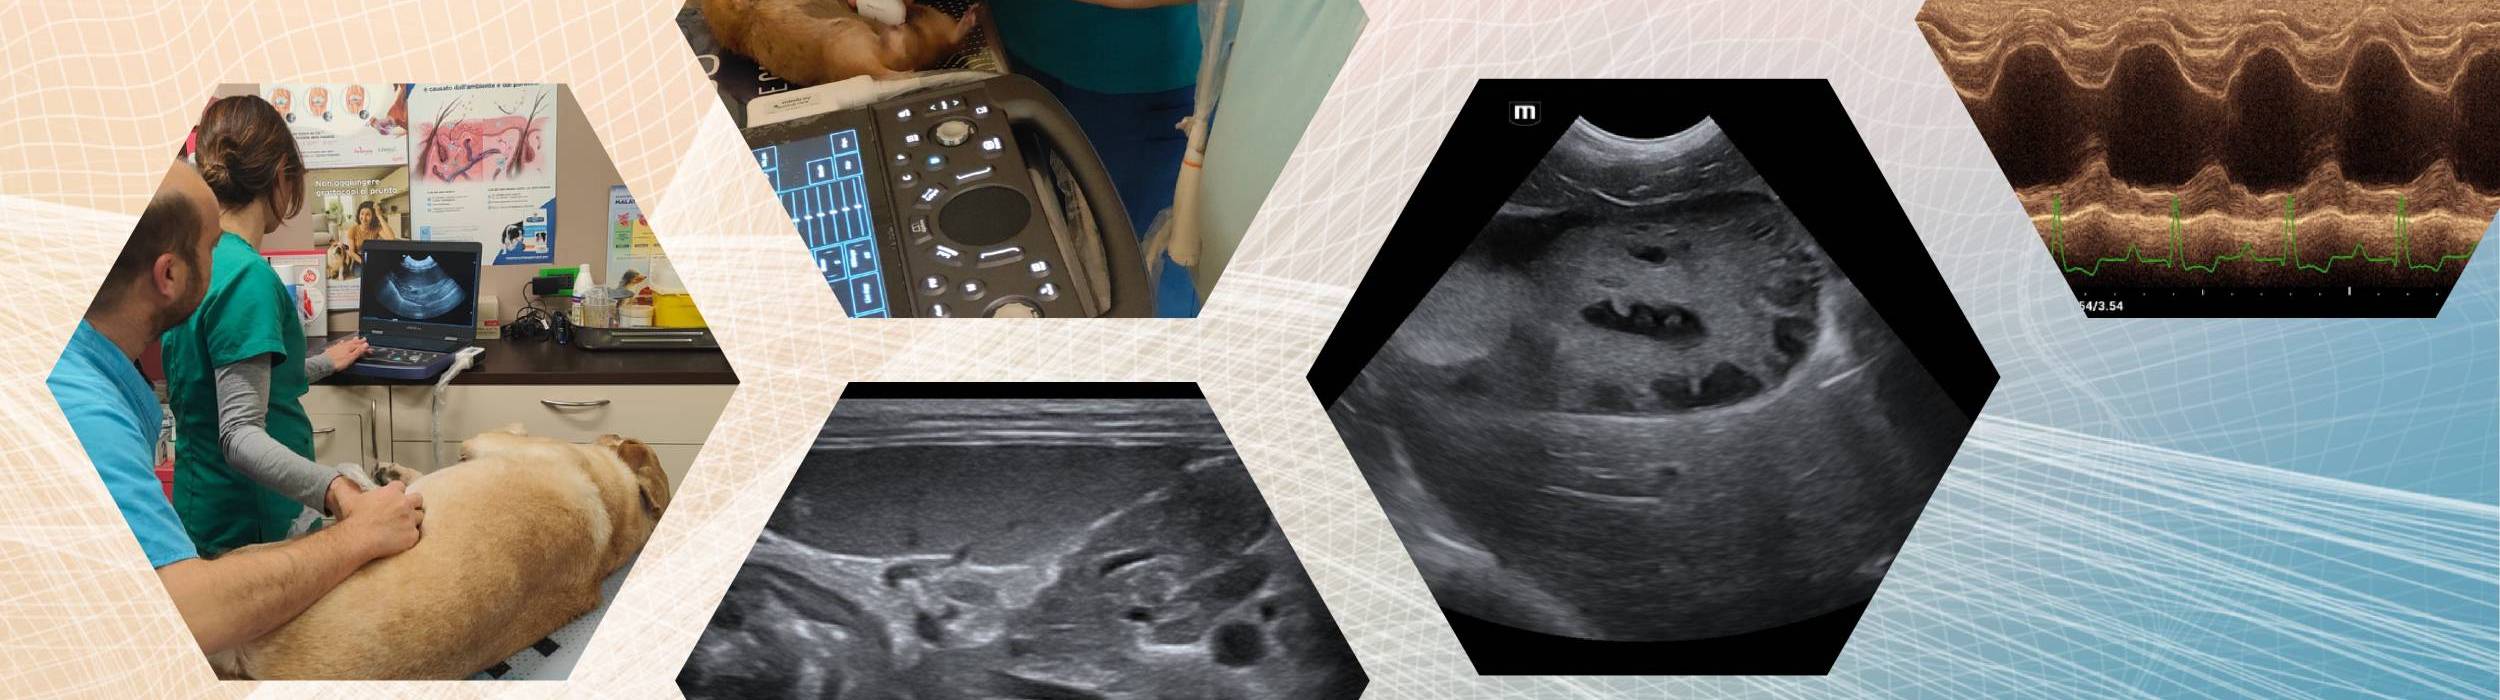

Un percorso formativo intensivo e altamente personalizzato, pensato per offrire un’esperienza didattica esclusiva in rapporto diretto 1:1 tra professionista e discente oppure tra professionista e struttura veterinaria richiedente.

Lo stage si svolge generalmente nell’arco di una o due giornate complete, con un’impostazione prevalentemente pratica e orientata alla realtà clinica quotidiana.

Formazione individuale dedicata al singolo veterinario, con affiancamento diretto durante l’attività ecografica o ecocardiografica.

Sessione formativa erogata direttamente presso la clinica richiedente, con focus sull’ottimizzazione dei protocolli diagnostici, del flusso di lavoro e dell’utilizzo della strumentazione disponibile.

• Ecografia addominale

• Ecografia internistica avanzata

• Ecografia interventistica

• Ecocardiografia di base o avanzata